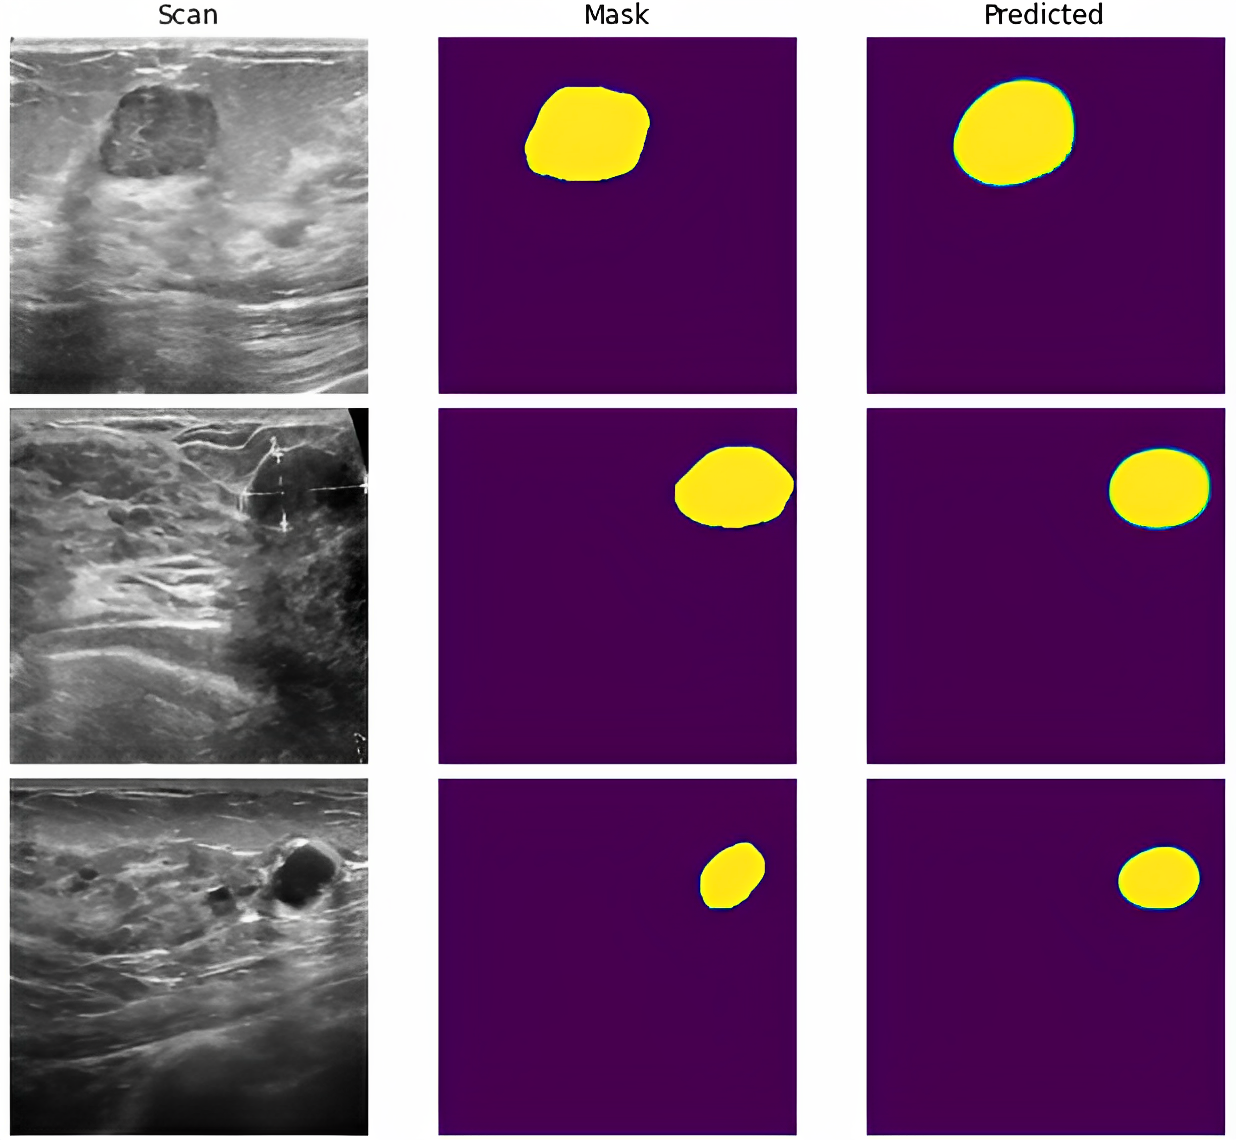

Refer to caption

Figure 5: Predicted outcome using Proposed Model

In Figure 5, the visualization of the segmented global test scans obtained from our proposed model are displayed. The visualization highlight the high accuracy achieved by our model in segmenting the USBCI, with minimal noise observed in the predicted images. Upon comparing the predicted images with the ground truth images or mask images, it is evident that our model successfully captures the essential features of the lesions. This is demonstrated by the remarkable alignment between the boundaries of the predicted and ground truth images, emphasizing the model’s ability to accurately identify and delineate BC lesions.